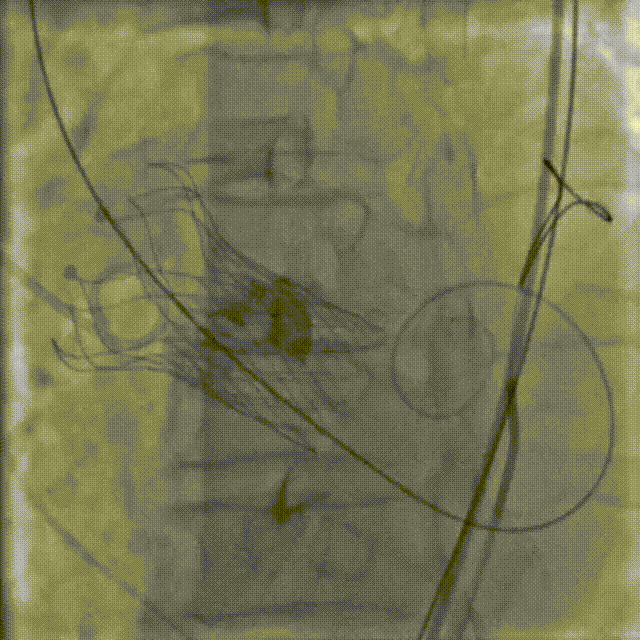

5.释放完成

瓣膜释放后造影提示冠脉⽆遮挡

最终瓣膜植入深度可,形态佳,⽆瓣周漏

6. 外周检查。

术后即刻评估

术后行主动脉根部造影未见明显夹层,压差从145mmHg降至10mmHg,无明显瓣周漏,且冠脉血流通畅;复查心脏彩超显示心功能指标较前明显提升,症状明显改善。